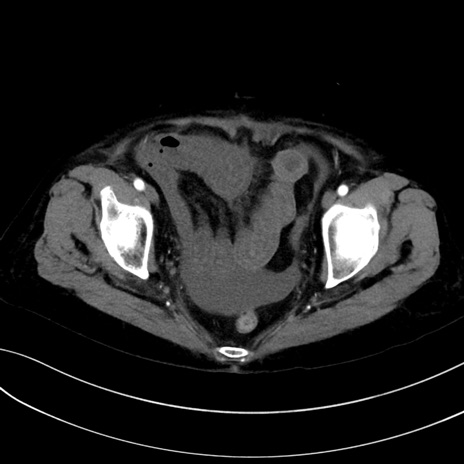

症例13 CT(横断像)1日半後